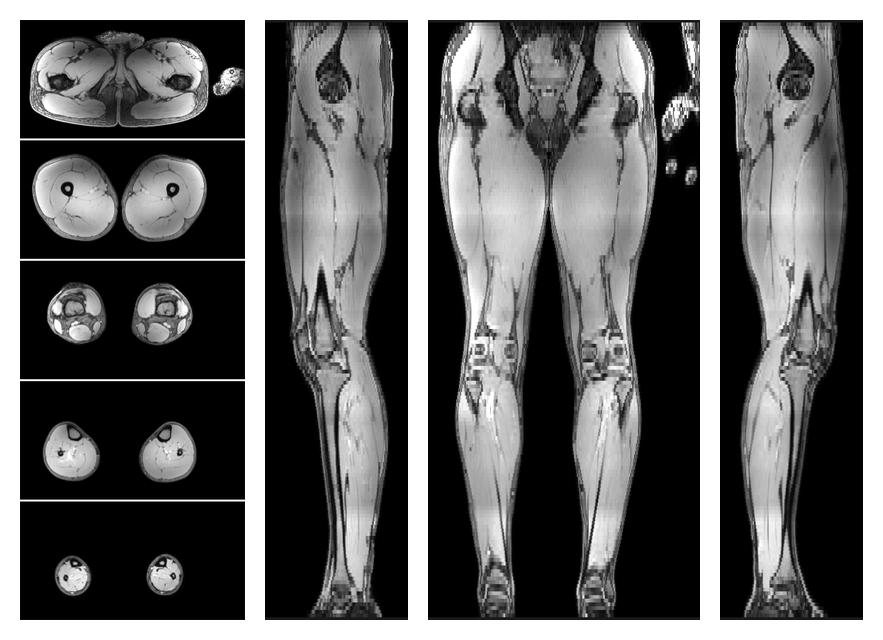

• Water only signal

The water part of the acquired multi-echo spin echo data.

• Water only T2 relaxation time

The water only T2 relaxation time of the lower extremity obtained from multi echo spin echo t2 mapping with EPG based reconstruction.